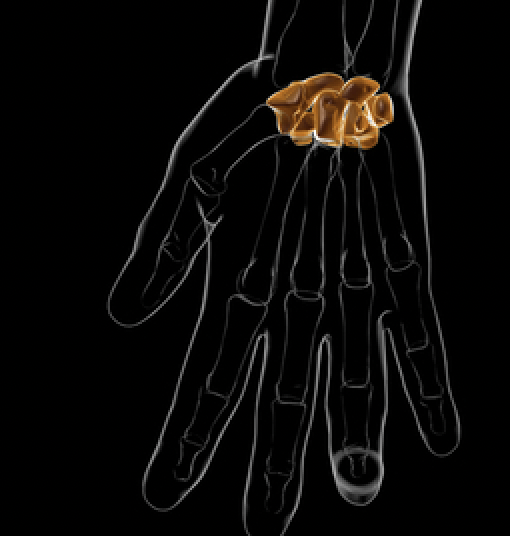

对于舟骨骨折,我们是否还应该固定拇指,还是只固定腕部石膏就同样有效?

文章:Harper, KJ、Rees, Y.、Tan, NX、Li, H.、Fonseca, EA、Quach, PG、Lee, GS、Brayshaw, JR 和 McGarry, S. (2025)。 ...

斜方掌关节融合术后 MCP ROM 的变化

快速回顾:斜方掌关节融合术后 MCP ROM 的变化 Hayashi, M.、Kato, H.、Komatsu, M.、Yamazaki, H.、Uchiyama, S. 和 Takahashi, J. (2021)。变化 ...